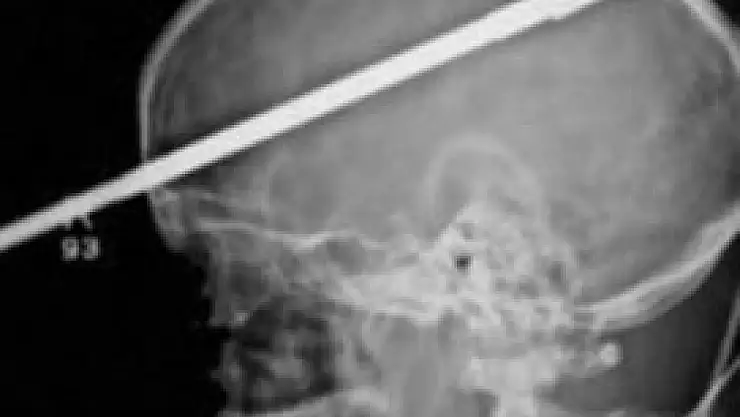

Zıpkını temizlemesi sırasında yanlışlıkla ateş etmesi sonucu sol gözünden kafasına 15 santimetre uzunluğunda mızrak saplanan Coutinho, olay sonrası bilincini kaybetmeden halasına bağırmayı başardı. Hemen hastaneye kaldırılan Coutinho, tedavi altına alındı. Doktorlar Coutinho’nun gözünden 10 saatlik operasyon sonrası mızrağı çıkarmayı başardı. Coutinho’nun beyninde bir hasar oluşmadığını ifade eden doktorlar, şanslı adamın sol gözünü fiziki olarak kurtardıklarını fakat görme yetisini kaybettiğini açıkladılar